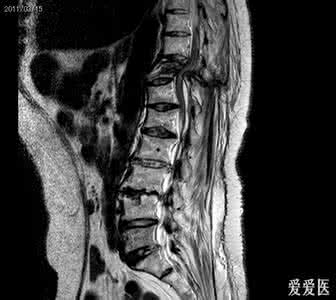

根据致伤场所及机制、临床特点及影像学所见不难以作出诊断。一张清晰的X线侧位片即可明确受损部位及椎节分裂程度。伴有脊髓症状者,应行CT扫描或MRI检查。